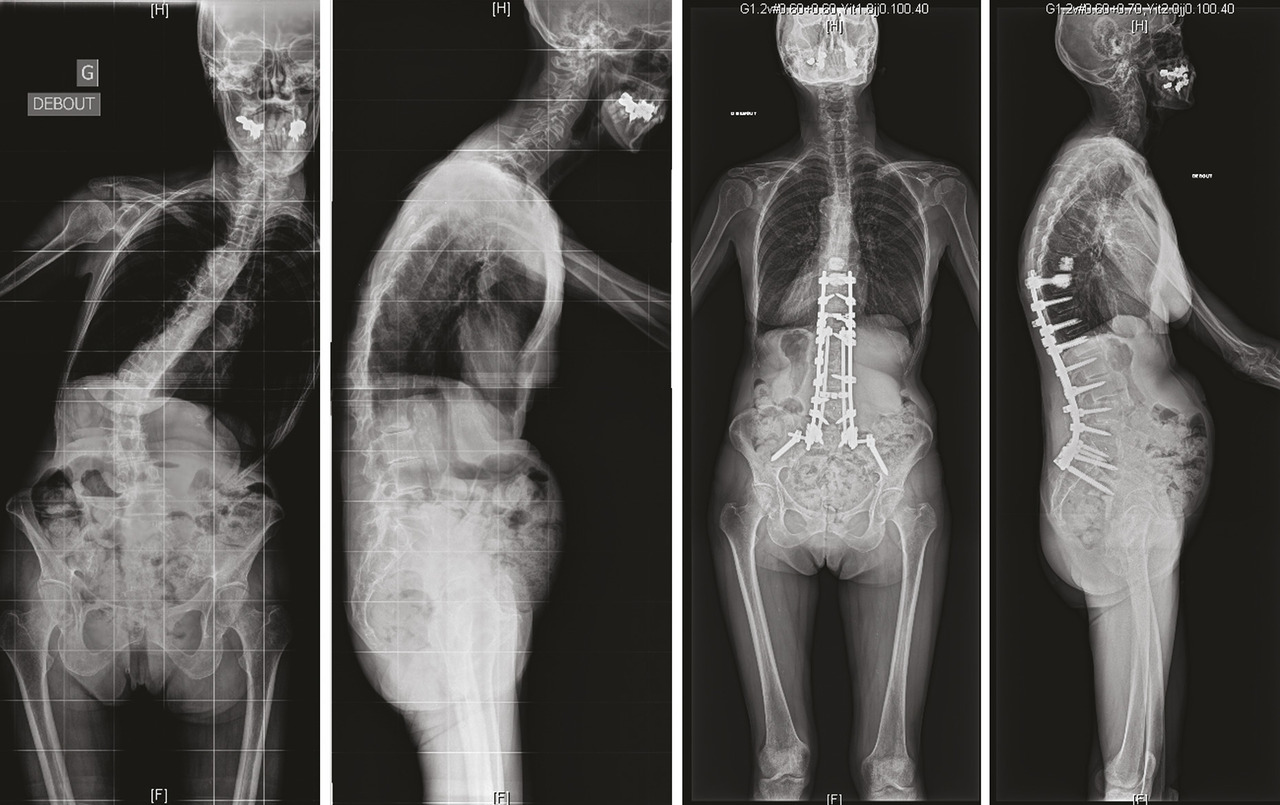

L’arthrose n’est pas seulement responsable d’ostéophytes rétrécissant le canal, elle s’accompagne aussi d’usure articulaire. Le rachis est alors déstabilisé. Le mouvement anormal est responsable de douleurs rachidiennes. Le déplacement engendré peut aboutir à une sténose fixée ou dynamique (spondylolisthésis dégénératif) limitant le périmètre de marche. L’usure du disque et des articulaires décoapte les vertèbres qui se déplacent l’une par rapport à l’autre. Cette déformation se fait le plus souvent vers l’avant (déséquilibre antérieur) mais aussi en rotation pour donner lieu à une scoliose dégénérative de novo ou accentuer une scoliose existante.

Les muscles spinaux peuvent être atteints de dysplasie graisseuse à l’origine d’un effondrement du rachis (camptocormie ou syndrome du sphinx). Encore une fois, cette déformation, en dehors de la douleur et de la limitation du déplacement, est une atteinte à l’image de soi et accélère le vieillissement.

L’ostéosynthèse moderne permet de fixer solidement le rachis. Les vis pédiculaires,5 au besoin aidées par le cimentage du corps vertébral, sont utilisées couramment dans tous les services de chirurgie du rachis. L’immobilité obtenue est le meilleur moyen de lutter contre la douleur.6 Mais l’ostéosynthèse permet aussi la réduction de la déformation dans les trois plans de l’espace (fig. 3 et 4 ). L’équilibre rachidien restitué facilite la reprise de la marche et redonne une vie plus facile au patient qui a subi dans son dos le poids des ans.7 L’ostéosynthèse est solide et permet un lever immédiat en règle générale sans contention externe. Une greffe osseuse pérennise le montage le protégeant d’un démontage ou d’une fracture du matériel.

L’ostéosynthèse moderne permet de fixer solidement le rachis. Les vis pédiculaires,5 au besoin aidées par le cimentage du corps vertébral, sont utilisées couramment dans tous les services de chirurgie du rachis. L’immobilité obtenue est le meilleur moyen de lutter contre la douleur.6 Mais l’ostéosynthèse permet aussi la réduction de la déformation dans les trois plans de l’espace (